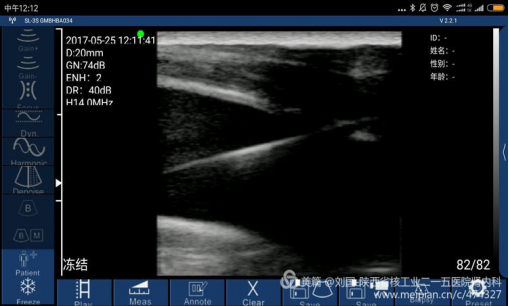

索诺星无线超声所查的结果,显示器是我的小米max。

索诺星的真面目